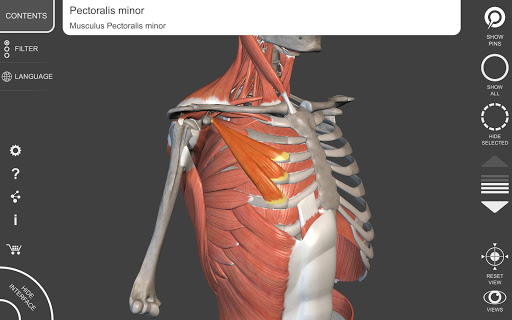

يتيح لك "Anatomy 3D Atlas" دراسة التشريح البشري بطريقة سهلة وتفاعلية.

من خلال واجهة بسيطة وبديهية، من الممكن ملاحظة كل بنية تشريحية من أي زاوية.

تتميز النماذج التشريحية ثلاثية الأبعاد بتفاصيل خاصة ودقة تصل إلى 4K.

نماذج تشريحية ثلاثية الأبعاد

• الجهاز العضلي الهيكلي

• تصور العضلات من خلال مستويات الطبقات من الطبقات السطحية إلى الأعمق

• من خلال تحديد نموذج أو دبوس، يظهر المصطلح التشريحي ذي الصلة

• وصف العضلات: الأصل والإدخال والتعصيب والعمل